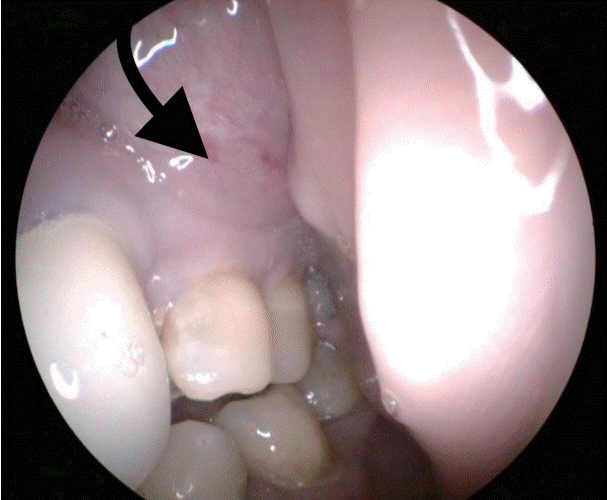

64세 여자 환자가 내원 5주 전 외부 치과에서 치아 신경치료를 받던 중 좌측 상 잇몸 및 안면 부종이 발생하여 콘빔 전산화단층촬영을 시행하고 절개 배농을 시도하였으나 실패하였다. 이에 영상상 발견된 부비동염 소견으로 타 외래에서 내원 2주 전 부비동 전산화단층촬영을 시행 후 양측 상악동 부비동염 의심 소견으로 내원하였다. 환자는 기저질환으로 고혈압, 당뇨 외 1992년 난소암으로 자궁전적출술 및 양측 난소 절제술 후 cyclophosphamide, adriamycin, cisplatin 3제 복합화학요법, 2003년에 유방암으로 절제 생검을 받은 과거력이 있었으며, 흡연력은 없었고, 가족력상 특이 소견은 없었다. 내원 당시 환자는 코 불편감을 호소하지 않았으며, 약간의 압통을 동반한 좌측 안면 부종 및 구강 시진상 좌측 제1, 2 소구치 주위 부종 소견(Fig. 1)을 보였으며, 비강 내시경상 좌측 비중격 만곡 외에 특이 소견은 없었다. 부비동 전산화단층촬영에서 양측 상악동에 골 점막 비후 및 연조직 음영을 동반한 석회화 소견이 관찰되었으나, 골 파괴 소견은 관찰되지 않았다(Fig. 2). 이에 환자에게 양측 상악동 진균성 부비동염 의심소견에 대한 수술적 치료의 필요성을 설명하였으나 환자는 치과 치료 후 발생한 좌측 안면 부종에 대한 우선적인 치료를 강력히 원하였고, 이에 치성 농양을 의심하에 본원 구강외과에 진료를 의뢰하였다. 이후 본원 구강외과에서 25번 치아 주위로 3번의 절개 및 배농으로 고름과 다량의 육아조직을 제거하고 항생제 치료를 하였으나 호전과 악화를 반복하였다. 6주 후 좌측 협측골의 누공이 상악동 내로 연결된 소견이 추가로 관찰되어 이비인후과로 다시 의뢰되었다. 재진료 시 여전히 코 불편감은 없었으나 좌측 안면 부종은 더욱 악화되었고, 비강 내시경상 좌측 중비도에 약간의 부종 소견을 보였다. 이에 양측 중비도 개창술을 계획하였다. 우선 우측 중비도 개창술 후 진균구로 의심되는 갈색의 석회화된 병변을 제거하였고, 이어서 좌측 중비도 개창술을 시행하였는데 진균구 의심 병변과 함께 매끈한 표면의 다소 견고한 연조직이 상악동 내부를 가득 채우고 있었다. 동결절편검사 결과, 해당 조직이 소세포암임이 진단되어 가능한 한도 내에서 미세절삭기를 이용해 일부 제거 후 수술을 종료하였다. 최종 조직검사 결과 hematoxylin & eosin 염색에서 세포질이 적고 핵이 과염색 되는 원형 및 방추형의 작은 세포가 관찰되었으며(Fig. 3A), 면역조직화학염색상 cytokeratin(Fig. 3B), CD56(Fig. 3C), synaptophysin(Fig. 3D)에 양성으로 폐외소세포암으로 진단되었다. 추가적으로 진균구에 대한 hematoxylin & eosin 염색상 균사는 아스페르길루스종으로 확인되었다(Fig. 3E).

술 후 당일 시행한 조영 증강 경부 전산화단층촬영에서 좌측 상악동, 상악동 앞쪽 부위 및 협부 점막에 걸쳐 조영이 증강되는 5.5 cm 연조직 종괴가 관찰되었고(Fig. 4A), 좌측 측경부와 인두후부에 다수의 림프절 전이 소견이 관찰되었다(Fig. 4B). 조영 증강 부비동 자기공명영상촬영에서는 동일 부위에 T2 강조영상에서 중간 신호 강도를 보이고(Fig. 5A), T1에서 저신호 강도를 보이며, 조영제를 사용한 T1 강조영상에서 조영 증강되는 연조직 종괴를 확인하였다(Fig. 5B). 술 후 5일째 시행한 양전자방출단층촬영에서 좌측 상악동, 전상악동 부위, 협부 점막 및 좌측 경부 림프절(Fig. 6A)에 fluorodeoxyglucose 섭취 증가와 함께 간과 비장(Fig. 6B)의 전이 의심 소견이 보였다. 폐의 우상엽 부위에는 수술 당일 조영 증강 경부 전산화단층촬영에서 보이지 않고 새롭게 관찰되는, 염증성 결절 의심 소견이 있어 조영 증강 흉부 전산화단층촬영을 추가로 시행하였고, 양성 병변이나 전암성 병변배제 위해 3개월 뒤 추적 관찰을 권유받았다. 이에 최종 좌측 상악동에서 기원한 폐외소세포암(cT4aN2bM1)으로 진단되었다. 이후 환자가 원하여 항암 치료를 위해 타 병원으로 전원되었다.